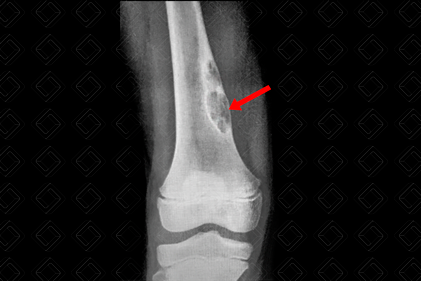

Descrição da figura: Radiografia do joelho direito AP. Aparência radiográfica clássica de um fibroma não ossificante na metáfise femoral medial distal (seta vermelha).

Fibroma não ossificante: L esão óssea benigna, com predileção pelos ossos longos (preferencialmente, fêmur distal medial, tíbia, fêmur proximal e úmero proximal). Quando essas lesões são menores que 3 cm, recebem o nome de defeito cortical fibroso . [cms-watermark]

• Radiografia dos ossos longos: Lesão óssea lítica , em geral, na região metafisária periférica , com leve esclerose marginal. O eixo longitudinal do tumor é paralelo ao eixo longitudinal do osso. Não há sinais sugestivos de malignidade como ruptura da cortical óssea ou reações periosteais suspeitas (figura acima);